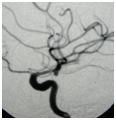

A 78 year-old woman suffering from hypertension was admitted on the seventh day. Undergoing drowsiness, right moderated hemiparesis and bilateral VI CN paresis and Glasgow Coma Scale (GCS): 10pts. On CT scan was categorized as grade III in Fisher scale and presented diffuse and dense cisternal clot with predominance on the left side. The angiogram showed bilateral carotid siphon aneurysms on posterior communicating artery (PComA) segment and vasospasm (Figure 1 and 2). The left PComA aneurysm was clipped, showing significant clinic evolution. According to the modified Rankin Scale (mRS) on the late sixth month follow up, the patient is graded 2 and fully recovers from the VI CN paresis at the same time.

Figure 2 Left side Pcom Aaneursysm.